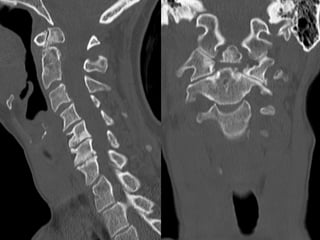

55 year old woman with central axial neck pain with

no radiculopathy; no signs or symptoms of myelopathy.

No history of trauma PMH: hypothyroidism in general

healthy

55 year oldwoman with central axial neck pain with no radiculopathy; no signs or symptoms of myelopathy. No history of trauma PMH: hypothyroidism in general healthy